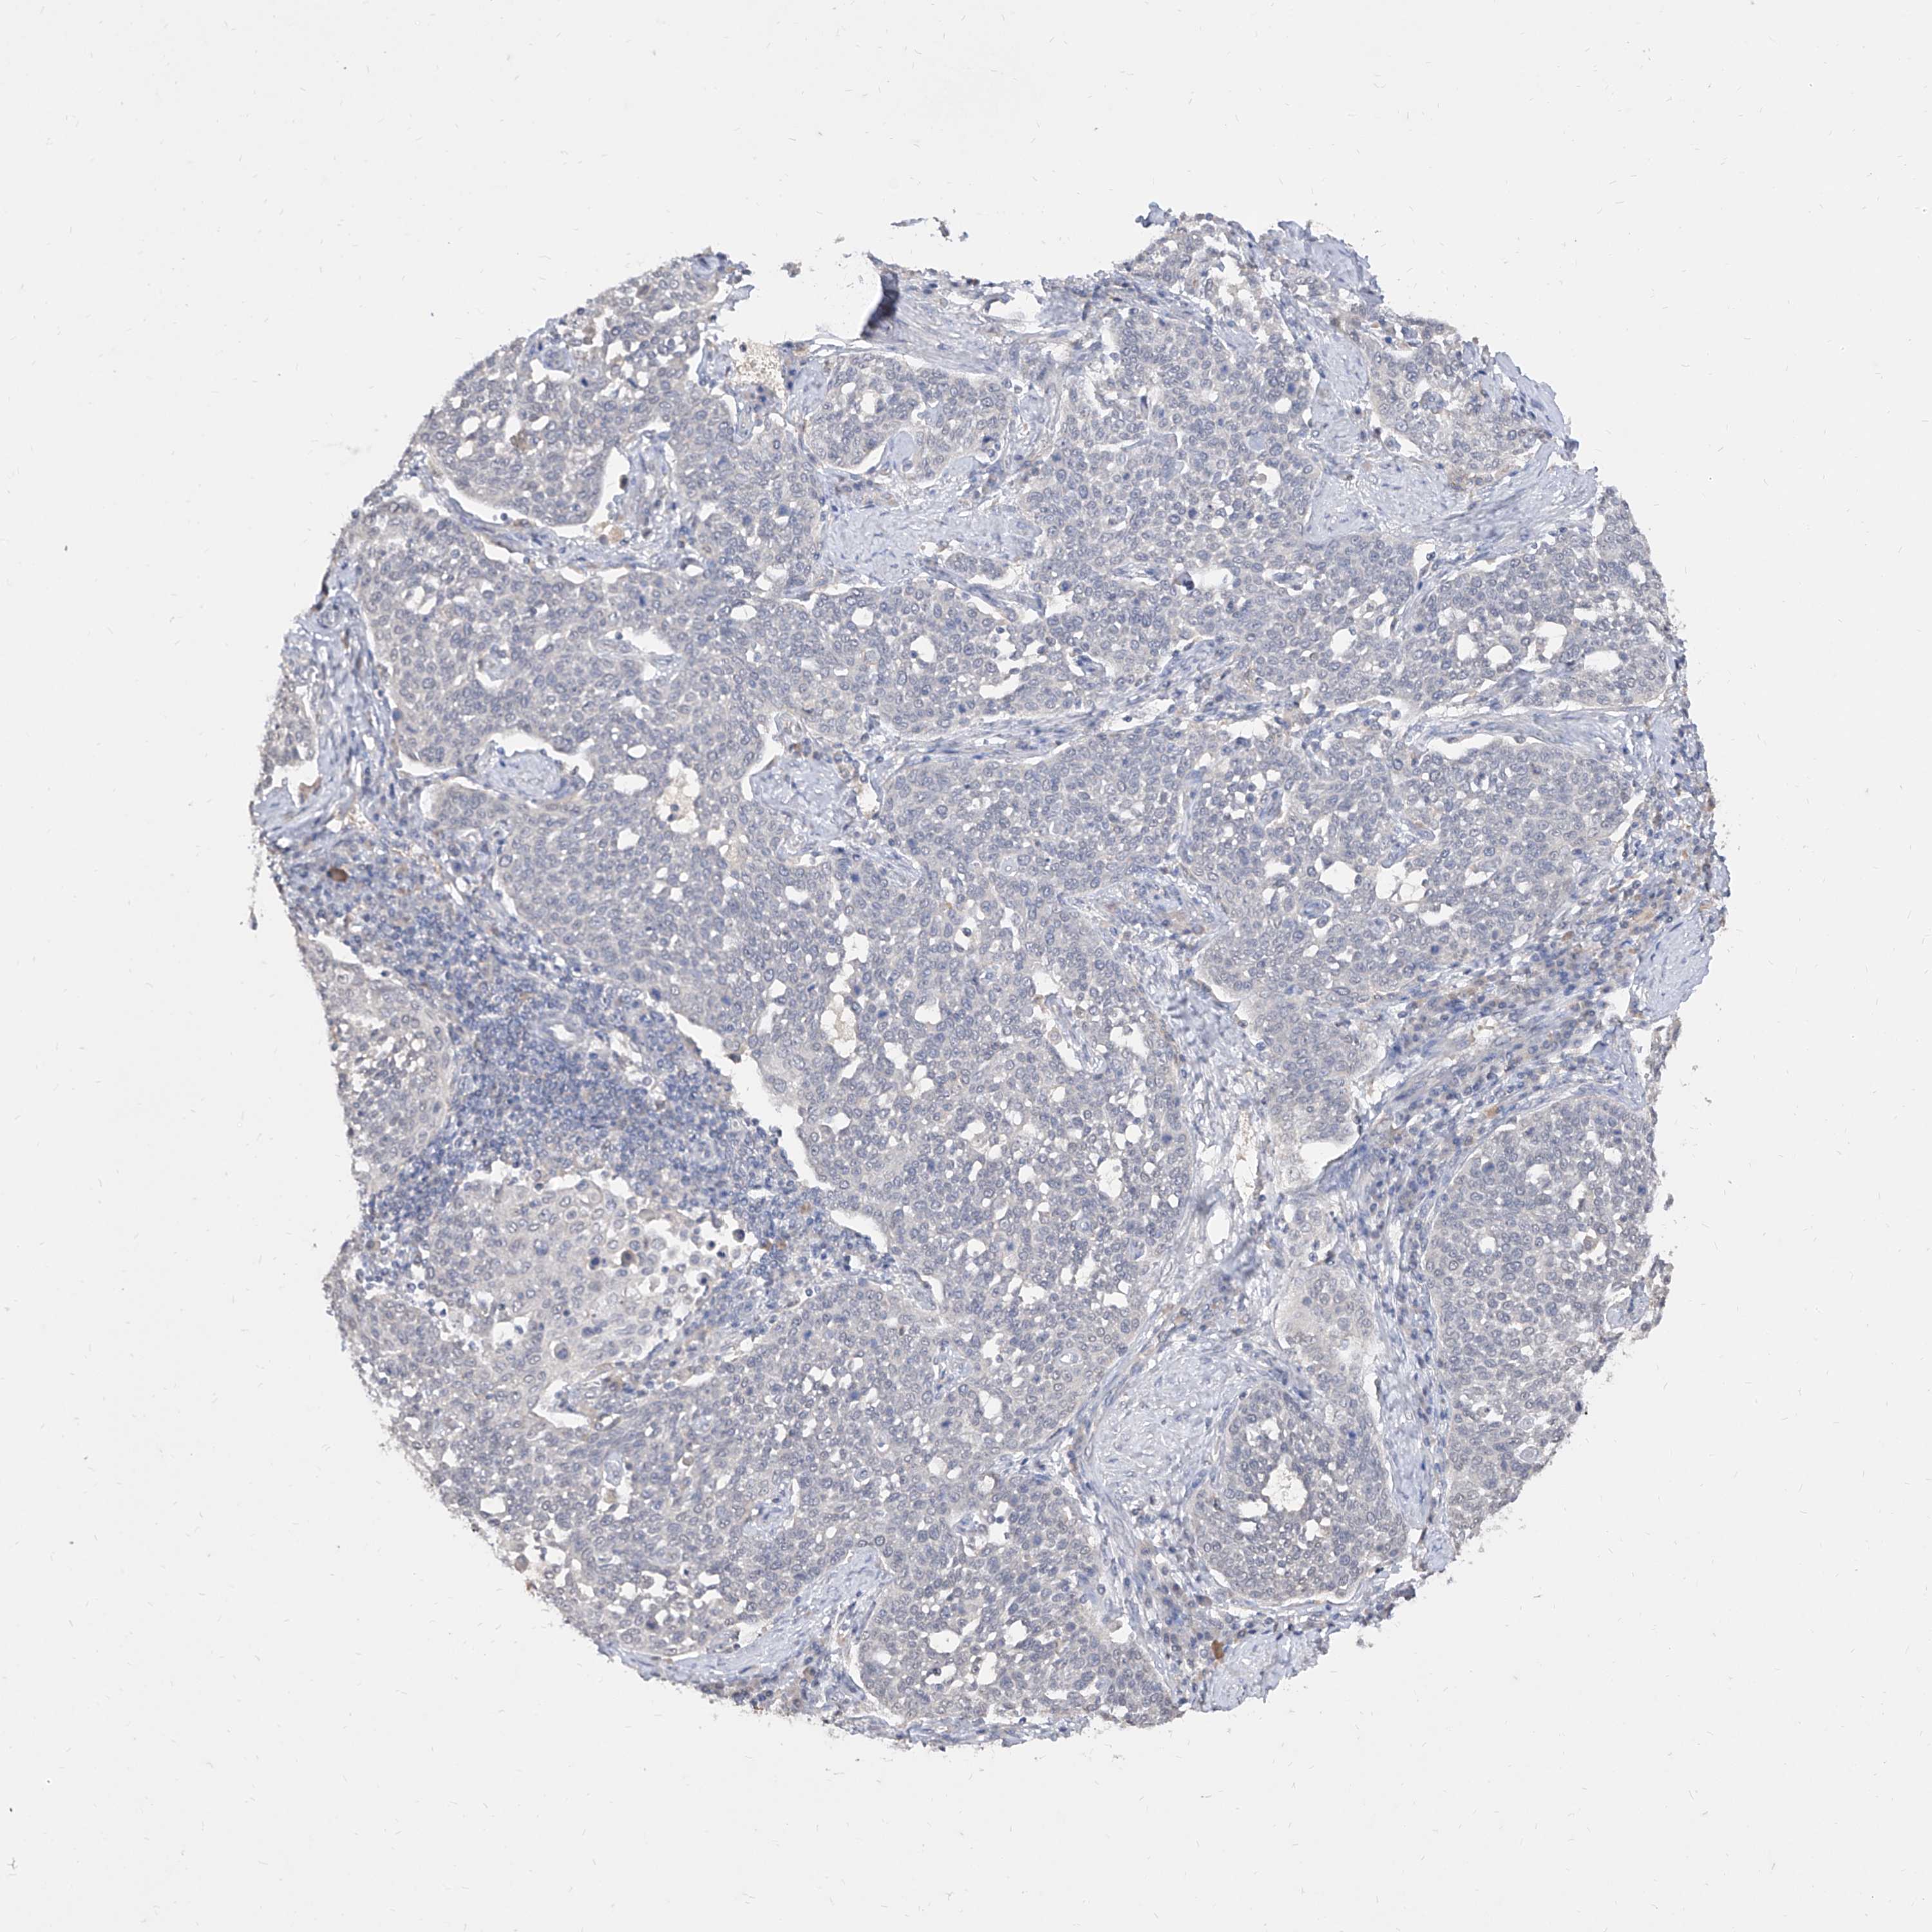

CERVICAL CANCER - Protein expressioni

A mouse-over function shows sample information and annotation data. Click on an image to view it in a full screen mode. Samples can be filtered based on level of antibody staining by selecting one or several of the following categories: high, medium, low and not detected. The assay and annotation is described here.

Note that samples used for immunohistochemistry by the Human Protein Atlas do not correspond to samples in the TCGA dataset.

Antibody stainingi

Antibody staining in the annotated cell types in the current human tissue is reported as not detected, low, medium, or high, based on conventional immunohistochemistry profiling in selected tissues. This score is based on the combination of the staining intensity and fraction of stained cells.

Each image is clickable and will lead to virtual microscopy that enables deeper exploration of all samples and also displays staining intensity scores, fraction scores and subcellular localization as well as patient and tissue information for each sample.

Adenocarcinoma, NOS